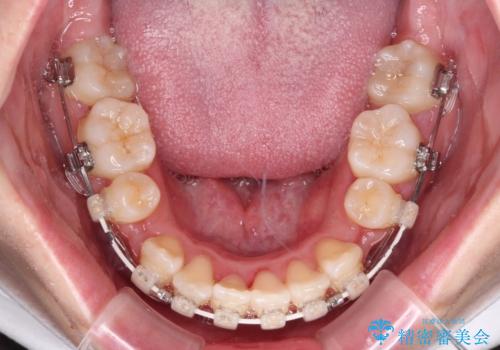

- 矯正装置

- 審美装置

- 治療期間

- 2年2ヶ月

舌の突出癖を改善するためのトレーニングをしっかりと行っていただいたことで、比較的スムーズに治療を進めることができました。